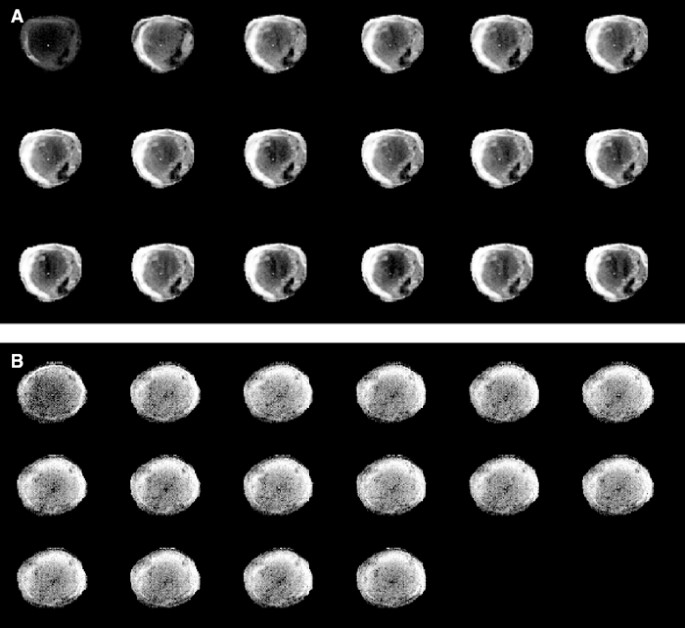

Perfusion of EL-4 and E.G7-OVA tumours was assessed by monitoring the inflow of an MRI contrast agent, Gd-DTPA, following intravenous injection between days 10 and 12 after tumour implantation. The inflow of the agent was measured using a series of rapidly acquired, T1-weighted, spin echo images, in which the increase in signal intensity was proportional to the concentration of the contrast agent. Typical image series for an EL-4 tumour and an E.G7-OVA tumour, which went on to regress, are shown in Figure 3. The increased signal intensity in the regressive E.G7-OVA tumour (Figure 3A) shows clear evidence of vascular proliferation in the tumour periphery. Histological analysis also showed that the vascular proliferation accompanying immune rejection occurred predominantly at the tumour edge (data not shown). These MR images show, in a qualitative way, that tumour perfusion was increased in the E.G7-OVA tumour that went on to regress, when compared to the nonregressing EL-4 tumour. This was confirmed, in a more quantitative way, by plotting mean signal enhancement across the whole tumour vs time, for 5 EL-4, 5 E.G7-OVA progressive and 5 E.G7-OVA regressive tumours (Figure 4). Signal enhancement in the regressive E.G7-OVA tumours was significantly greater (P<0.0001, one way ANOVA) than in either the EL-4 or progressive E.G7-OVA tumours. These data can be used to estimate perfusion quantitatively by converting the increase in image pixel intensities, in the presence of the agent, into R1p values, as described previously (Kennedy et al, 1994; Beauregard et al, 1998, 2001) and in Materials and Methods section. R1p is the paramagnetic contribution to the longitudinal relaxation rate and is directly proportional to the concentration of the contrast agent. The centres of these tumours were relatively poorly perfused and therefore estimates of R1p values in these regions had a large error associated with them, as we have observed previously in other tumours (Beauregard et al, 2001, 2002). Therefore, perfusion was assessed by measuring the mean increase in R1p values in a 20 pixel-wide band in the tumour periphery. Plots of the mean increase in R1p values, following intravenous injection of Gd-DTPA, in EL-4, progressive E.G7-OVA and regressive E.G7-OVA tumours, are shown in Figure 4. These show that there was a significant (P<0.001, n=5, ANOVA) increase in the perfusion of those E.G7-OVA tumours that went on to regress, when compared to EL-4 and progressive E.G7-OVA tumours. These data were also analysed to estimate tumour vascular volumes, using the model described by Su et al (1994). The pharmacokinetic data of Furman-Haran et al (1996) for Gd-DTPA in mouse plasma were used to derive an arterial input function. The vascular volumes of regressive E.G7-OVA tumours were significantly higher than those of both EL-4 (P<0.01) and progressive E,G7-OVA tumours (P<0.01, Student's t-test). The vascular volumes of the progressive E.G7-OVA tumours were also significantly higher than those of EL-4 tumours (P<0.05). The vascular volumes determined by MRI were similar to those obtained using the carmine dye injection technique for the regressive EG7-OVA tumours, but significantly higher than those obtained using the dye in the EL-4 and progressive E.G7-OVA tumours (see Table 2). This may reflect the fact that the MRI estimate was taken from the tumour periphery, where vessel density is higher.

A series of T1-weighted MR images acquired from a regressive E.G7-OVA tumour (A) and an EL-4 tumour (B) following i.v. injection of the MRI contrast agent, Gd-DTPA. The first images in the series were acquired prior to contrast agent injection. The subsequent images (reading from left-to-right and top-to-bottom) were acquired at 2 min intervals. The presence of the contrast agent increases signal intensity in the images and these increases are proportional to its concentration.